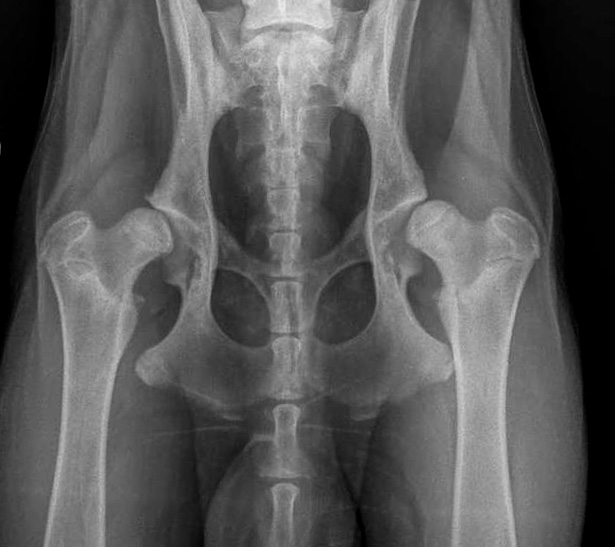

Hier nun einige HD Röntgenbilder:

![]() HD-C/ HD-leicht/HD-2 (ab diesem Befund wird im ADRV e.V. kein Hund mehr zur Zucht zugelassen) |

![]() HD-D/ HD-mittel/ HD 3 |

C |

= Grad1 (leicht) |

HD-2 |

leicht |

Leichte Inkongruenz, divergierender Gelenkspalt, NORBERG-Winkel um 100 Grad |

D |

= Grad2 (mittelgradig) |

HD-3 |

mittel |

Gravierende Veränderungen mit arthrotischen Zubildungen, NORBERG-Winkel zwischen 90 und 100 Grad |